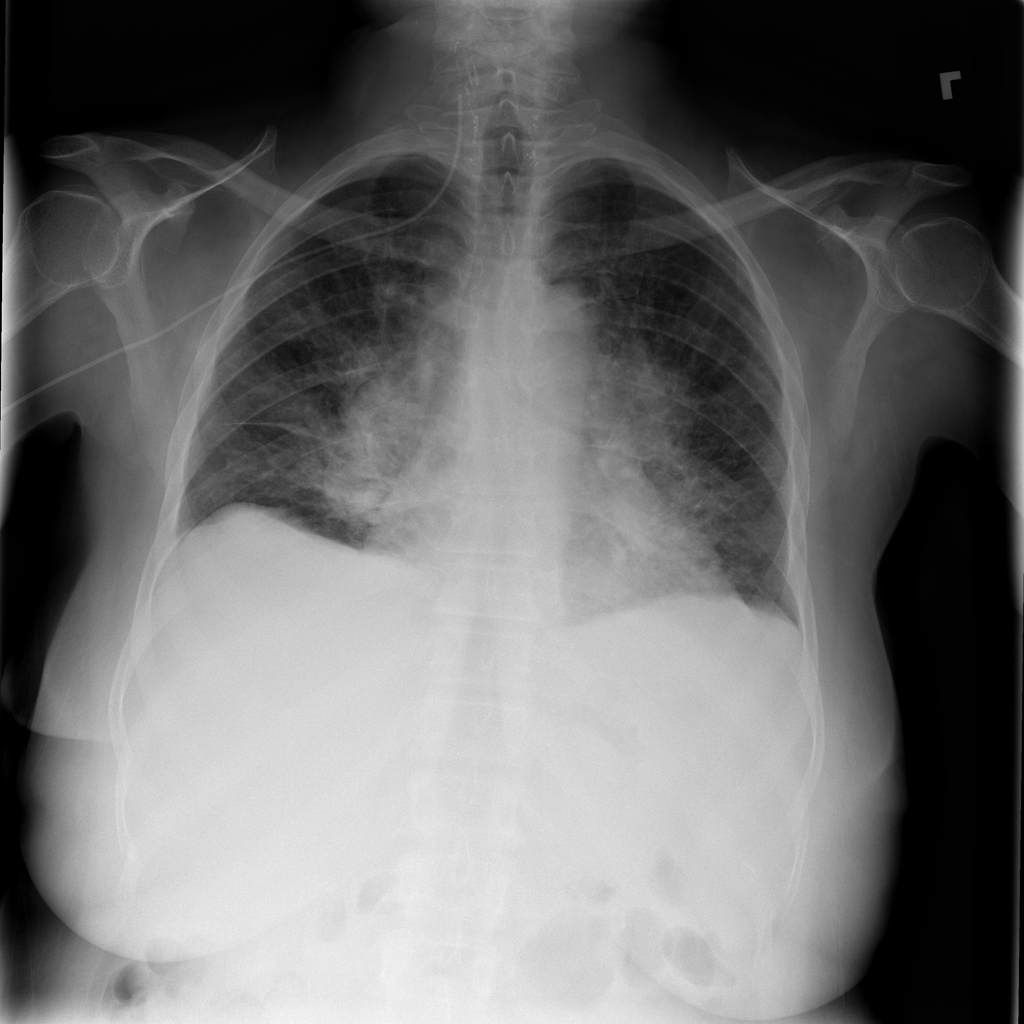

Mass

A mass is a larger focal opacity or lesion seen on the image. It is a descriptive finding that can have several causes and usually needs more imaging or clinical context to characterize.

PAT-50E5 · IMG-008Mass

PAT-50E5 · IMG-008

PA